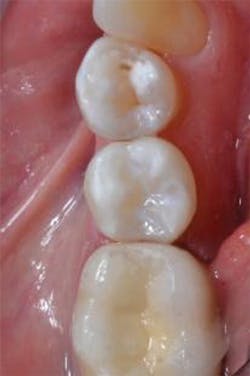

Figure 13: View of teeth Nos. 4 and 5 after curing the final occlusal layer of TPH Spectra composite.

Figure 14: Final restorations on teeth Nos. 4 and 5.